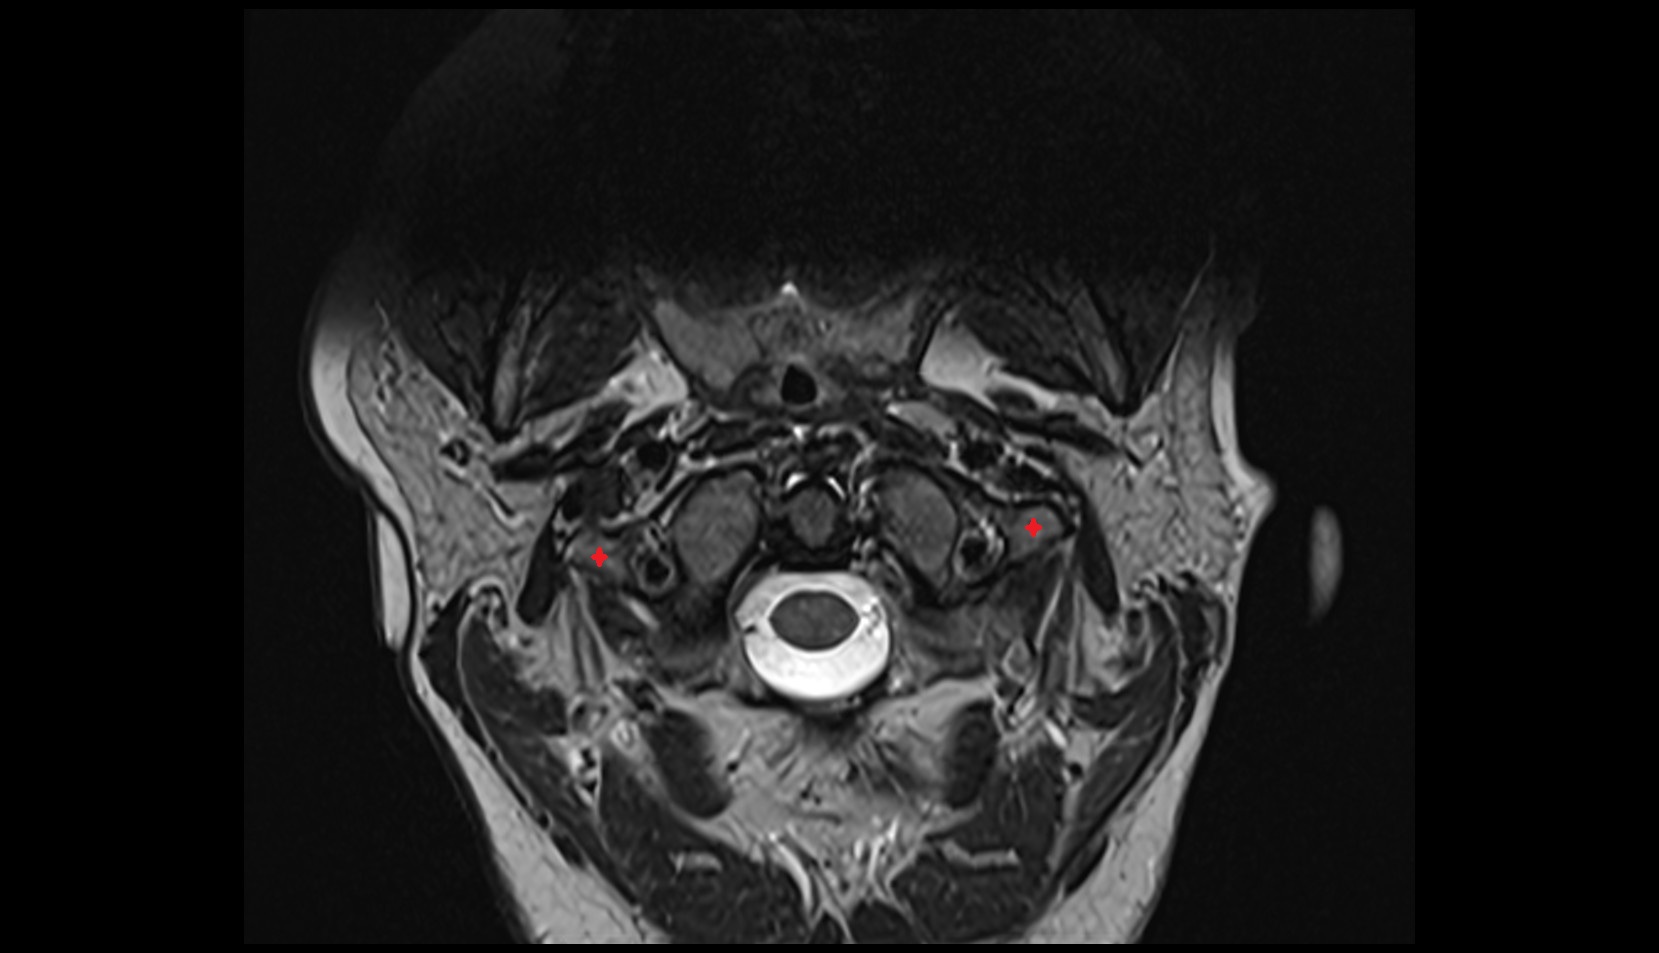

- Temporomandibular joint

- Mandibular condyle

- Mandibular fossa